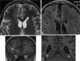

Panhypopituitarism

Hypopituitarism is the decreased (hypo) secretion of one or more of the eight hormones normally produced by the pituitary gland at the base of the brain. If there is decreased secretion of one specific pituitary hormone, the condition is known as selective hypopituitarism. [Source: Wikipedia ]